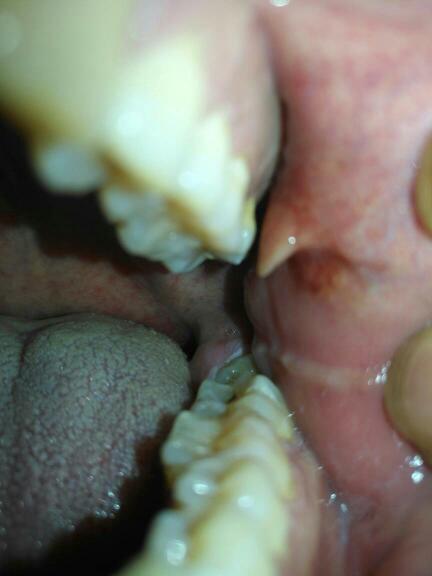

图一口腔里今天发现长了个小肉疙瘩摸起来硬不疼这是什

口腔两侧长小肉疙瘩且不痛不痒,可能是正常结构或疾病表现,需结合具体特征判断,建议及时就医明确病因若为正常结构,可能无需特殊处理例如,异位皮脂腺表现为颊部黏膜小米粒大小的透明小疱,属良性生理变异皮脂腺增生则呈现淡黄色或...